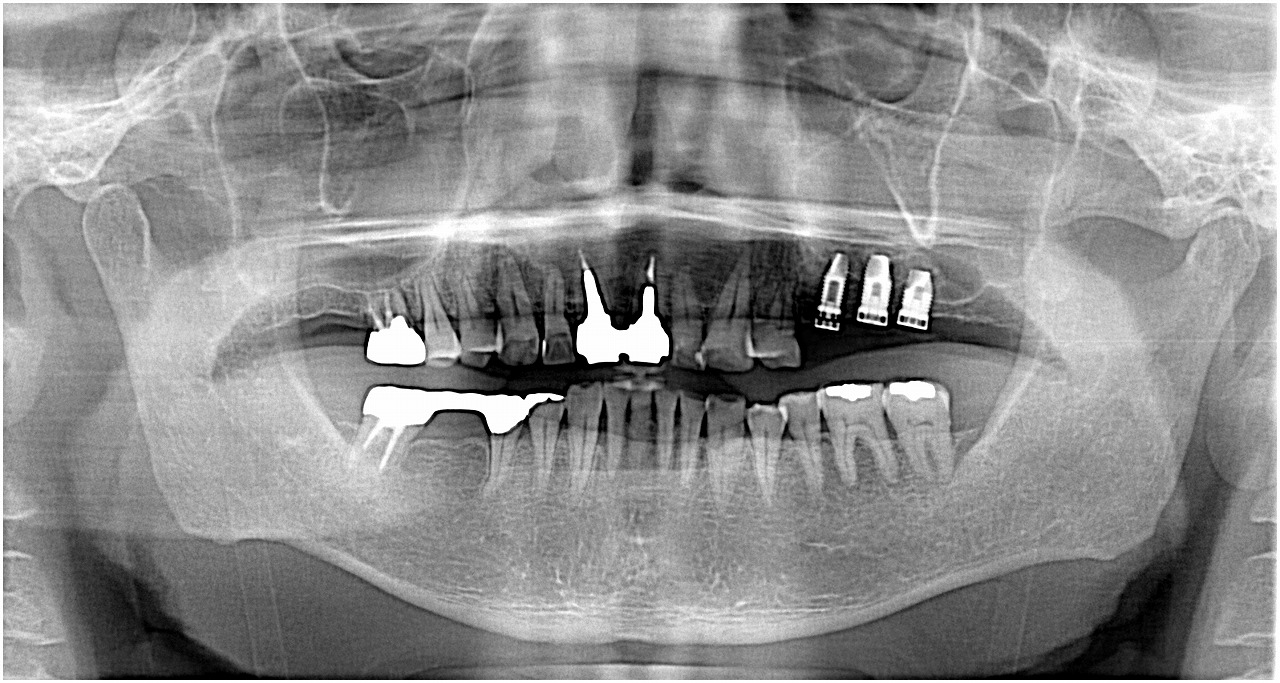

術後のパノラマになります